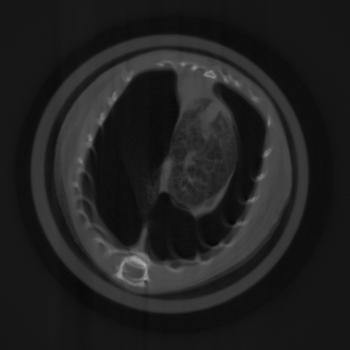

To evaluate the location of the lung tissue in the two mice computed tomographies (CT) of them were performed. This was done by rotating the object and acquiring 601 angular projections equally spaced over a full circle with the setup described in Section II.3. A reference image was taken after every 15th projection. This leads to a total of to acquire all projection images. For image reconstruction, a filtered backprojection (FBP) was applied using a ramp kernel for the absorption and the dark field data and a Hilbert kernel for the phase data after performing the phase retrieval described in Section II.2.

Exemplary for the data, one set of axial cross-sections of the lung region of the second mouse are displayed in Figure 5 (marked as horizontal lines in Figure 4). In all three CT cross-sections, the lung tissue can clearly be located in the chest of the mouse. The location found with the CT reconstruction corresponds with the location visible in the dark field projection image and the speckled area in the differential-phase image. In contrast, the exact position of the lung cannot be located with the absorption image alone.

To quantify the location of lung tissue within the mouse, a CT scan of the second mouse was performed. Its results, shown in Figure 5, substantiate the above results that lung tissue is, indeed, only present in the right part of the mouse’s chest cavity in this cross-section plane. It is imaginable that an assured diagnosis can be made without a computed tomography scan, which could lead to a quickened diagnosis and a dose saving.